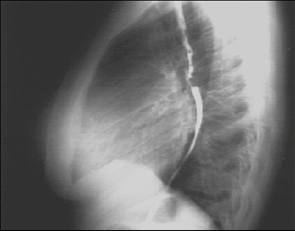

Chest X Ray

Labs - X Rays

PA and Lateral

Click on the xrays to enlarge them.

Choose the best interpretation of the chest X rays:

Left atrial enlargement and right ventricular enlargement

Left ventricular enlargement and pulmonary congestion

Calcified mitral annulus

Left ventricular enlargement and dilated aorta

Left ventricular enlargement and left atrial enlargement